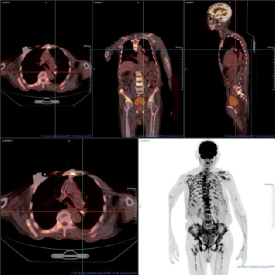

影像学佐证

(附PET/CT图像:前列腺前部正中局灶性高代谢灶SUVmax6.80、全身骨骼多发高代谢灶及纵隔及肺门多发淋巴结异常摄取。)